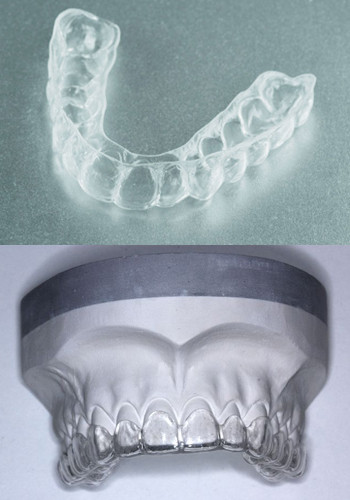

Entlastungsschienen für das Kiefergelenk, meistens bereits ausreichend